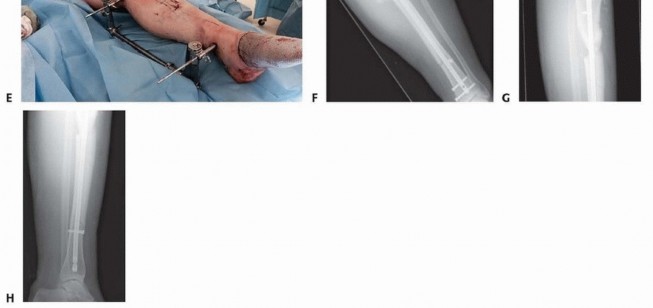

### TECH FIG 6 • Reduction of a simple middle diaphyseal fracture. A. AP radiograph of an oblique spiral distal tibia fracture. B. Use fluoroscopy to demonstrate fracture lines and localize clamp incision locations and clamp positions. C. Pointed reduction clamps can be placed through small stab incisions. D,E. AP and lateral fluoroscopic image demonstrating fracture reduction with percutaneous clamp application. Fracture Reduction ### Simple Middle Diaphyseal Fractures (Transverse or Short Oblique) Manual traction with gross manipulation will reduce simple transverse mid-diaphyseal fractures. Medially based external fixation or distraction with a large universal distractor is helpful for reduction when no assistants are available, in large patients, or when used for provisional fixation. Muscular paralysis is often helpful. Placement of percutaneous pointed reduction forceps can be helpful in oblique and short oblique patterns to achieve anatomic or near-anatomic reduction. Use fluoroscopy to mark the level and orientation of the fracture on the skin to facilitate the reduction clamp orientation and ideal placement of skin incisions. Introduce a small or large pointed clamp under and through skin stab wounds; care must be taken to maintain clamp points against bone ( TECH FIG 6A-C). Typically, the spike on the distal fragment is posterolateral. ### Highly Comminuted Middle Diaphyseal Fractures Have comparison radiographic images of the uninjured extremity available to be used as a template for length and rotational reduction landmarks. 556 Mechanical traction with medially based half-pin fixation is very helpful. A large external fixator or large universal distractor is equally effective. The proximal Schanz is placed posteriorly and parallel to the tibial plateau ( TECH FIG 7A). The distal Schanz pin is placed just above and parallel to the plafond ( TECH FIG 7B). The intramedullary reduction tool available in most nail or reamer sets can be used to manipulate the proximal fragment in order to advance the tool across the fracture, which achieves fracture reduction and guidewire placement. ### Open Middle Diaphyseal Fractures Large segmental and butterfly fragments that are completely devitalized and void of soft tissue attachments should be removed and cleaned of contamination. These pieces can be reintroduced into the fracture site and used to perform anatomic open reduction following passage of the intramedullary rod and interlocking. These pieces should be removed after fixation is completed because they represent a large amount of nonviable material in a high-risk wound.

### TECH FIG 7 • A. AP radiograph of a comminuted segmental tibial fracture. B-D. Intraoperative AP and lateral fluoroscopic imaging of the knee and lateral view of the ankle showing appropriate application of the large universal distractor with resultant reduction. A posteriorly positioned half-pin is helpful for fracture reduction and does not block nail passage. E. Clinical image showing application of large universal distractor. F-H. Postoperative AP and lateral radiographs of the knee and tibia showing successful fixation. Occasionally, an osteotome is required to free near-circumferential fragments ( TECH FIG 8A-C). If reduction is difficult, a small fragment unicortical plate can be used to maintain the reduction during reaming and nail placement. Once interlocking is completed, the plate should be removed ( TECH FIG 8D). Passing the Guidewire Once optimal AP and lateral plane reduction is achieved, the wire is advanced past the level of the fracture. Verify that the wire is within the canal on both the AP and lateral views to avoid advancing too far and damaging extramedullary structures. In metadiaphyseal fractures, the wire must be centered in the metaphyseal segment. In proximal and distal fractures, blocking screws or half-pins may be required to ensure centralized positioning of the guidewire ( TECH FIG 9A). 557

### TECH FIG 9 • A. A drill bit is used to ensure the guidewire is placed centrally in the distal segment of this distal metadiaphyseal fracture. B,C. The nail length guide is pushed to the opening of the tibia and verified with lateral fluoroscopic imaging. Device manufacturers supply nails in variable increments. When a length measurement falls in between lengths, choose the shorter length. A threaded end cap (usually 5, 10, and 15 mm) can be used if it is desired to bring the nail to top of the canal opening. Leaving the nail countersunk below the bone surface does not compromise stability in middle and distal fractures but may complicate future nail extraction. 558 Reaming the Canal Before reaming, estimate the narrowest canal diameter using both AP and lateral plain radiographs. Alternatively, intramedullary reamer sets typically have a radiolucent ruler that allows for intraoperative fluoroscopic verification, which should be done on both the AP and lateral views. The canal typically is reamed at least 1 mm over the isthmic diameter to minimize the risk of nail incarceration. Reaming should begin with an end-cutting reamer—the 8.5- or 9-mm size in most systems. Reamer heads should be evaluated before insertion and should be sharp and free of defects. Insert the reamer head into the proximal metaphysis with the knee in maximal flexion before applying power to avoid distorting the entrance hole ( TECH FIG 10A). Reamers are advanced at a slow pace under full power. If the reamer shafts are not solid, but are wound, be sure to avoid using reverse when drilling because that would cause the reamers to unwind if resistance is encountered within the intramedullary canal. Care must be taken not to inadvertently extract the guidewire when the reamers are removed. Multiple techniques are used. First, manual downward pressure can be applied to the wire with specialized instruments, medicine cups, or cleaning cannulas ( TECH FIG 10B). Once the reamer has cleared the opening, it can be clamped and held in position ( TECH FIG 10C). For the minimally reamed technique, a single end-cutting reamer (usually 9 mm) is passed down the canal to ensure the smallest diameter nail can pass through the narrowest segment of the intramedullary canal. In an effort to minimize thermal damage to the endosteal cortex, reaming should be discontinued within 0.5 to 1 mm of hearing the reamer head catching (“chatter”) on the endosteal cortex. Care also should be used when there are butterfly or oblique fracture fragments. Continued reaming after encountering chatter may result in iatrogenic comminution and loss of reduction.

### TECH FIG 10 • A. Maintenance of maximal knee flexion protects the entrance hole from being inadvertently enlarged by the reamer. B. If the guidewire is rotating during reaming, it must be held down as the reamer is pulled back to avoid inadvertent removal of the guidewire. C. A clamp can be used to grasp the guidewire when the reamer head clears the soft tissues. Unreamed Technique Standard preparation technique is used for the starting hole, and the fracture is reduced. Precise evaluation of the lateral isthmic diameter is repeated, and a small-diameter nail is selected, typically in the 7- to 9-mm range. A good guideline is to use a nail 1 to 1.5 mm smaller than the narrowest measure of the isthmus on the lateral radiograph. If lateral plane imaging is suggestive of canal diameter very close to nail size, a single pass with an end-cutting reamer usually is performed to decrease the possibility of nail incarceration. The nail is inserted and impacted in standard fashion. If significant resistance is encountered when the nail reaches the isthmus, the nail is removed to avoid incarceration or iatrogenic fracture propagation. A reamer 0.5 to 1.0 mm larger than the nail is passed down the canal, and nail passage is attempted again. Nail Insertion Once the nail insertion handle is attached, pass a drill through the proximal screw insertion attachment and screw insertion cannulas before inserting the nail to ensure accurate alignment of the attachment jig. Maintain nail rotation during insertion by aligning the center of the insertion handle with the tibial crest. Consider internal rotation of the nail if distal AP interlocking bolts are deemed necessary to minimize damage to distal neurovascular structures. Maintain knee hyperflexion during nail insertion to minimize the risk of posterior cortical abutment and iatrogenic fracture. Impact the nail to the final depth using lateral plane fluoroscopy. Interlocking Bolt Insertion In simple transverse fractures, place distal interlocks first to allow for backslapping for interfragmentary compression and gap minimization. Usually, distal interlock bolts are placed medial to lateral. Position the leg in slight extension and stable neutral rotation. 559 Rotate the C-arm to lateral imaging position and pull the tube back away from the medial side of the leg to allow for drill placement. Rotate the leg and C-arm individually and sequentially to create a perfect circle image; optimize this view before drilling attempts ( TECH FIG 11A). After localizing the interlocking hole using a clamp and fluoroscopy, make an incision large enough to place the locking bolt. Use blunt clamp dissection until the cortex is reached. Use a sharp drill point and place the center of the point in the center of the circle. Hold the drill obliquely to the nail axis to simplify repositioning ( TECH FIG 11B). Once the central location is achieved; align hand and drill with imaging axis. Fluoroscopes with laser alignment guides can be helpful to assist with alignment by centering the laser on the skin incision and then placing the laser in the center of the back of the drill when preparing to drill the hole ( TECH FIG 11C). Drill to the midsagittal point in the tibia. Then, disengage the drill from the drill bit and check the fluoroscopic image. If the drill is accurately positioned in the center of the hole, advance the drill bit with power through the far cortex; avoid broaching the far cortex by impacting with a mallet to avoid iatrogenic fracture. Drill the second interlock hole using the same technique but maintaining a parallel axis with the first successful drill passage. Replace the drill with the appropriate depth gauge and check an AP image before screw length selection. Once interlock lengths and position are verified, “backslapping” can occur to optimize compression. Using the slotted mallet attachment on the insertion handle, superiorly directed mallet blows can be used while pressure is applied to the foot in order to compress the fracture site. Fluoroscopy should be used to monitor the amount of compression and the nail position proximally. If backslapping is planned, the nail should be slightly overinserted to avoid nail prominence after compression is performed.